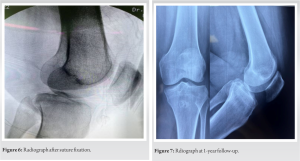

The patient was planned for open reduction and fixation. The patient was operated on under regional anesthesia in a prone position with a tourniquet over the proximal thigh. A lazy S-shaped skin incision was placed over the popliteal fossa with a horizontal limb over the fossa and vertical limbs over the lateral distal femur and proximal medial tibia (Fig. 2). The dissection was between the medial gastrocnemius and semimembranosus (Fig. 3) as suggested by Burke and Schaffer. Deep into this plane, the popliteus muscle was seen and elevated from the proximal tibia. The posterior capsule of the knee joint was identified along with the avulsed tibial fragment. The fragment was initially stabilized with a K wire (Fig. 4). Then, four high tensile sutures (Fiber wire No. 2, Arthrex, Naples, Florida) were passed through the posterior capsule and PCL at their tibial insertion on the avulsed fragment (Fig. 5).

A knotless fixation was planned with two swivel lock PEEK anchors (4.9 mm, Arthrex, Naples, Florida). Two drill holes were made and the drill holes were tapped for the passage of anchors. The sutures that were passed through the capsule and PCL were then passed through the anchors, with two sets of sutures through each anchor. The anchor along with the sutures was threaded through the posterior tibial cortex with sutures in tension and the K wire was removed (Fig. 5). The reduction was checked under the image (Fig. 6) and the tourniquet deflated. The wound was washed and closed in layers. A posterior knee plaster was applied with a proximal tibial posterior padding to prevent posterior sagging. The patient was started on isometric quadriceps exercises from day 1 and non-weight-bearing crutch walking was also started. At 2 weeks, the plaster was removed and sutures were also removed.